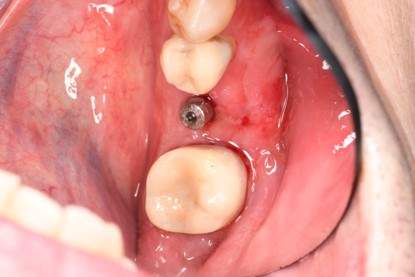

症例写真-2

- Befor

- 途中経過

- After

| 年齢 | 50代・男性 |

| 主訴 | 右下歯が疼く |

| 治療内容 | ・右下6番インプラント ※1:FGG(遊離歯肉移植術)とは、足りない歯ぐきを上顎から上皮を切り取り移植する外科手術 |

| 治療費 | 合計:902,000円(税込) ■内訳 |

| 治療期間 | 9ヵ月 |

| 治療方針 | 右下の当該歯は歯根破折により保存不可能と診断しました。歯周疾患も伴っていたため抜歯後に骨吸収※1が大きく起こることが予測できました。チタンメッシュ併用骨再生誘導法(GBR※2)を選択しインプラント埋入と同時に行い自然な歯槽骨のラインを再現しました。またGBRを行う際にインプラント辺縁の付着歯肉の減少が起こる為、遊離歯肉移植術(FGG※3)を行い清掃性を考慮した形態に仕上げました。 ■治療方針の解説 治療した右下の歯をレントゲンで撮影したところ根本の部分に黒く写る箇所があり「根尖性慢性周囲炎※1」と診断。また歯周病も進行していました。 ※1 骨吸収・・・歯槽骨という歯を支える骨がなくなっていくこと |

| 担当者所見 | 主訴の右下だけでなく歯茎の腫れ、発赤があり不良補綴や不良充填など他にも治療箇所が多数ありました。プラークコントロールが不良であった為まずはブラッシング指導を行いセルフケアの重要性を理解していただくところからスタートしました。 右下6番の歯はインプラント治療を行なった結果審美的にも機能的にも患者様の満足を得ることができました。骨造成と歯肉移植も行なった為インプラントを支える十分な歯周組織の獲得ができたと思っております。 |